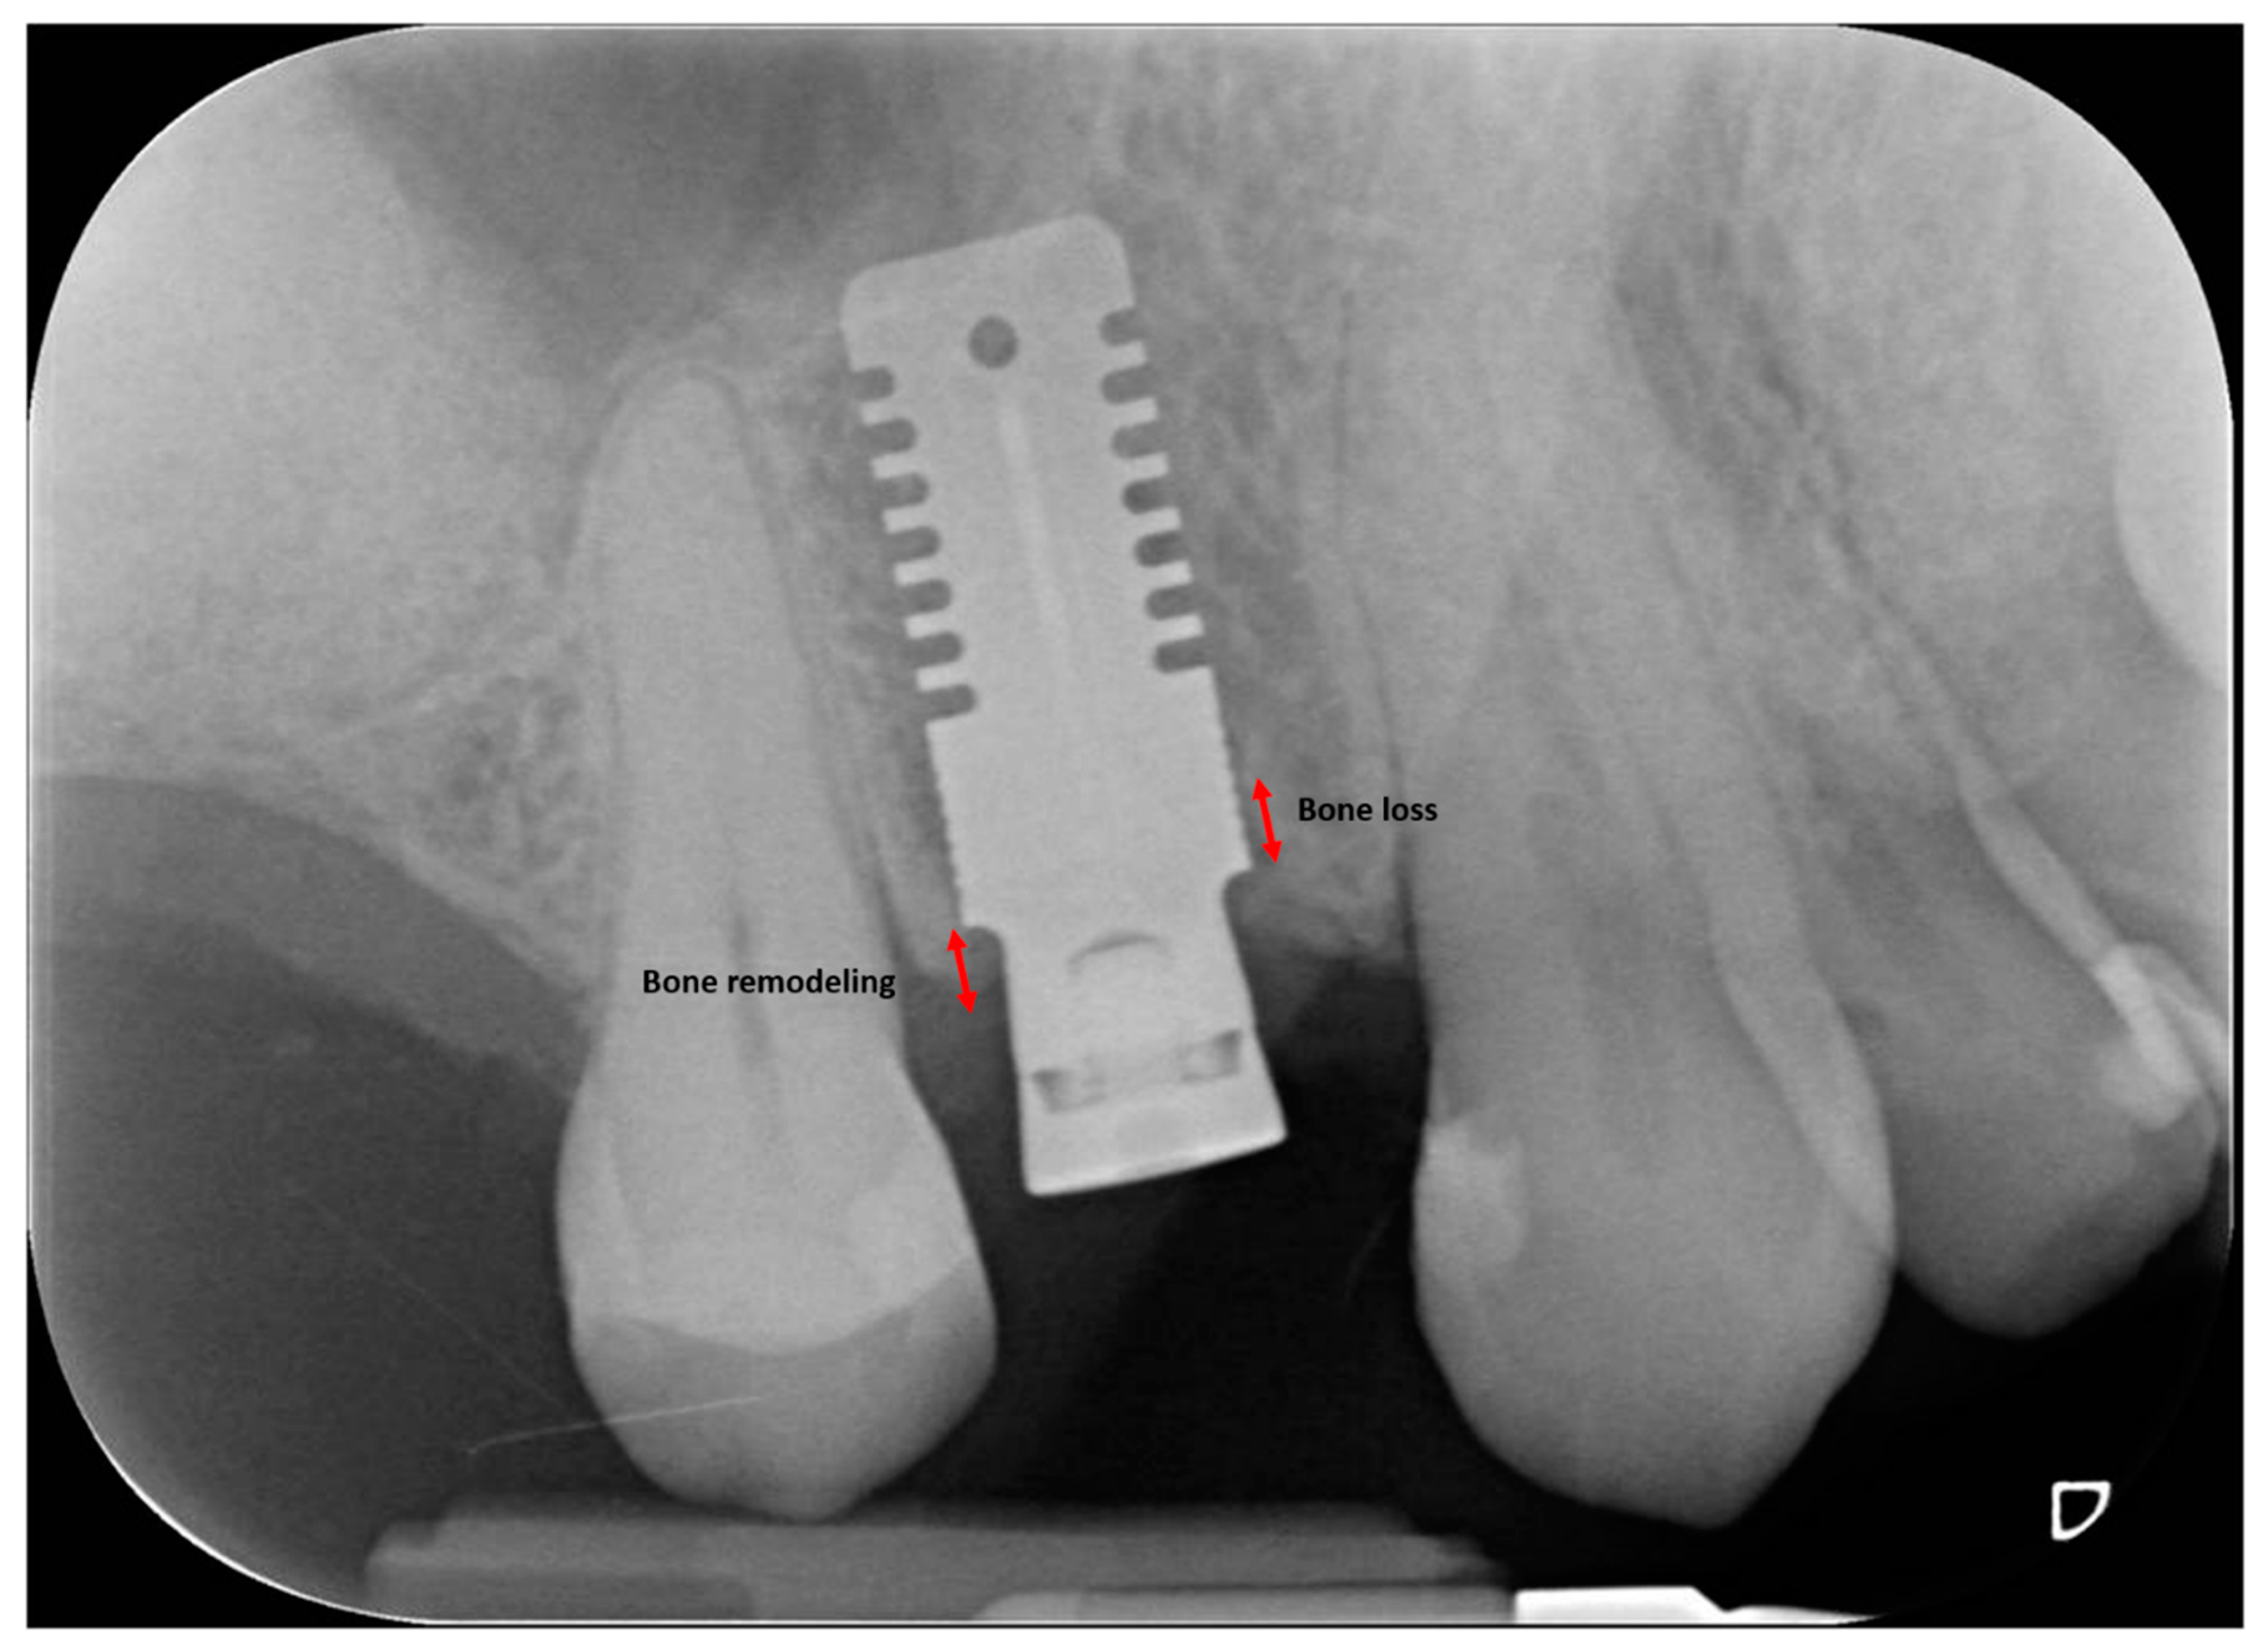

2.3. Radiographic Measurements

| MBL T1-T0 | 0.38 ± 0.46 | <0.001 * | 0.40 ± 0.58 | <0.001 * | 0.38 ± 0.48 | <0.001 * |

| MBL T2-T0 | 0.43 ± 0.57 | <0.001 * | 0.60 ± 0.74 | <0.001 * | 0.60 ± 0.52 | <0.001 * |

| MBL T2-T1 | 0.09 ± 0.22 | <0.001 * | 0.20 ± 0.36 | <0.001 * | 0.20 ± 0.19 | <0.001 * |